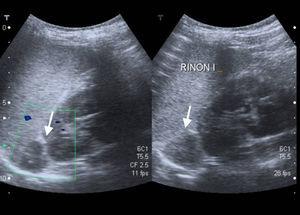

La ecografía, de fácil accesibilidad, sencilla realización y ausencia de radiación, tiene poca sensibilidad para la evaluación de las glándulas suprarrenales, más allá de los primeros meses de vida, por lo que no constituye la primera elección, si bien puede determinar la presencia de masas suprarrenales (fig. 3).